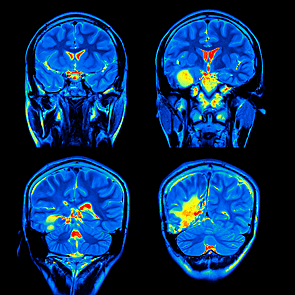

• Resonancia Magnetica

Resonancia Magnetica

La resonancia magnética es un examen que utiliza ondas de radio para crear imágenes muy detalladas de los órganos y estructuras que se encuentran en todas las partes del cuerpo humano.

Área de conocimiento: neuropsicología imagen tomada de: http://www.siacardio.com/